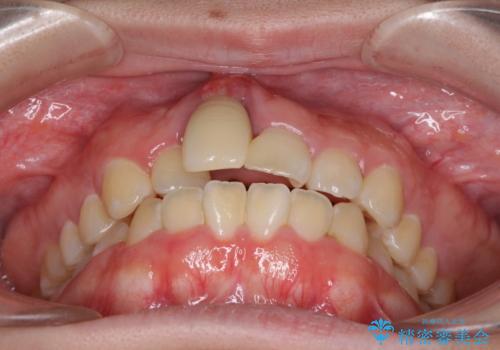

- 中学生の頃にぶつけた前歯に不格好なクラウンが装着されており、出っ歯な印象になっていることを気にして来院された患者様です。

ぶつけてしまった歯は保存が困難な状況であったので抜歯をし、ワイヤー矯正により歯列を整えつつ前歯の突出感を解消することとしました。

矯正治療後にはインプラント補綴治療を行うこととしました。

前歯の補綴治療はインプラントかブリッジかで悩んでいました。

周りの歯にむし歯がないため、インプラントがお勧めとなりますが、事故による骨欠損が大きく、歯肉ラインを整えるのが困難という問題がありました。